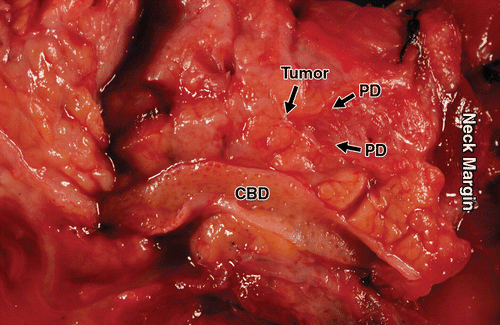

Pathologically, all lesions were found to be well-differentiated pancreatic neuroendocrine tumors. All six cases were remarkable for marked stromal fibrosis in the area of the neoplasm, which resulted in concentric narrowing of the pancreatic duct. Immunohistochemical labeling for serotonin revealed that the neoplasms all strongly and diffusely expressed serotonin (Figs. 2A, 2B, 2C, 2D, 5A, 5B, 5C, 5D, 5E, 5F, 6A, 6B, 6C, and 6D). An additional pathologic finding in two patients was chronic pancreatitis, presumably a result of duct obstruction (Figs. 5A, 5B, 5C, 5D, 5E, 5F, 6A, 6B, 6C, and 6D).

In previously reported cases of serotonin-producing pancreatic neuroendocrine tumors causing pancreatic duct obstruction and subsequent upstream duct dilatation or pancreatic atrophy, associated findings that might have contributed to obstruction of the main pancreatic duct included fibrosis [5, 6, 9] and compression of the pancreatic duct [8]. Takaji et al. [13] also found invasion serotonin-expressing pancreatic neuroendocrine tumors into the main pancreatic duct, something we did not observe.

We have been intrigued by the extent of duct dilatation and parenchymal atrophy encountered upstream of such small lesions. We believe the key phenomenon involved is a consequence of elaboration of serotonin by these small neoplasms [10]. Localized effects of serotonin or related metabolites induce a dense fibrotic response that constricts the pancreatic duct. The scarring and retraction are reminiscent of the process that occurs in the mesentery adjacent to deposits of small-intestinal carcinoid tumors [14]. The precise means by which serotonin or related products cause fibrous proliferation are not known [15]. Current thinking is that fibrogenesis is a consequence of the production of a number of substances, including serotonin, 5-hydroxyindoleacetic acid. and other components of the downstream signaling pathway [16].